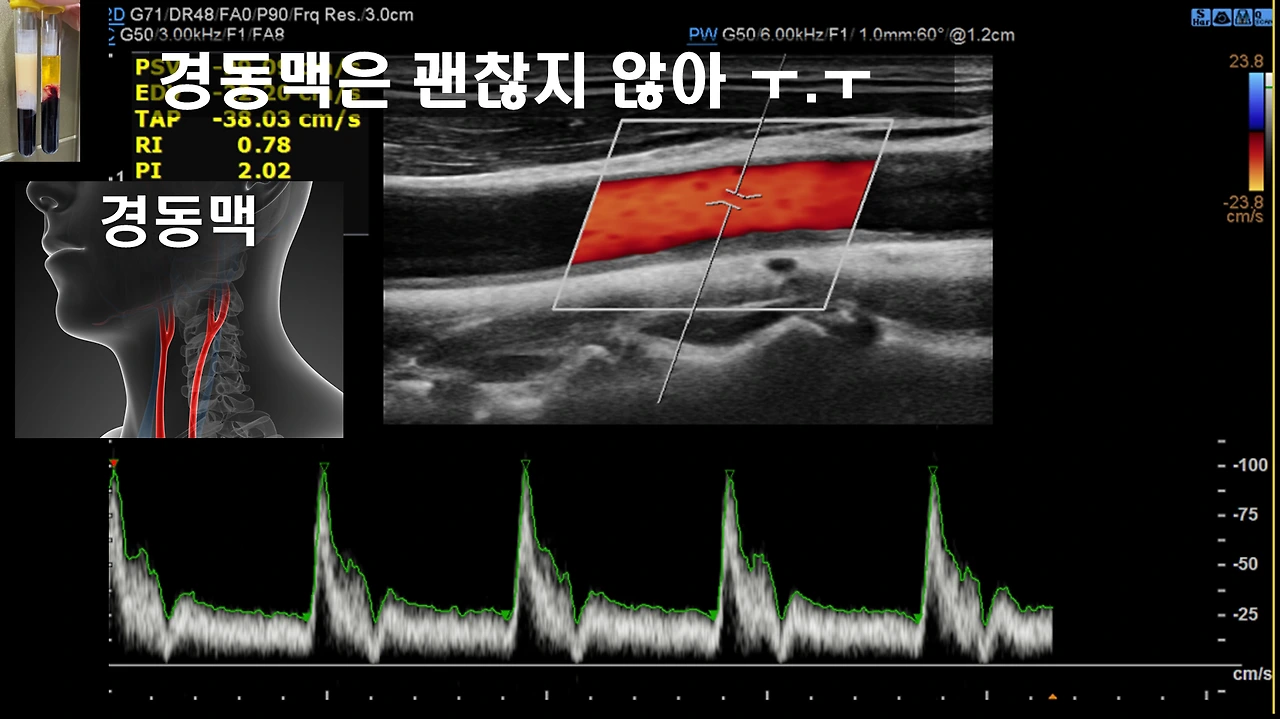

둘째, 실제 제 경동맥 상태

뇌혈관은 다행히 괜찮았지만 경동맥은 괜찮지 않았습니다. 저는 불행 중 다행으로 경동맥이 좁아졌지만 뇌혈관은 아직 좁아지지 않은 드문 경우입니다. 그러나 이대로 계속 지낸다면 뇌혈관도 좁아지는 것은 시간문제겠죠?

중년이 되면 경동맥의 안쪽 막이 1mm 미만이어야 하는데 저는 1.76mm로 확인되었습니다.

경동맥 초음파를 하면 혈류의 흐름을 확인할 수 있는데 아직 혈류 흐름은 나쁘지 않았습니다.

물론, 계속 진행한다면 혈류의 흐름이 불규칙해지고 혈관의 탄력성은 더 떨어질 테니 고혈압, 심근경색, 뇌경색 위험성이 자꾸 높아지겠죠.